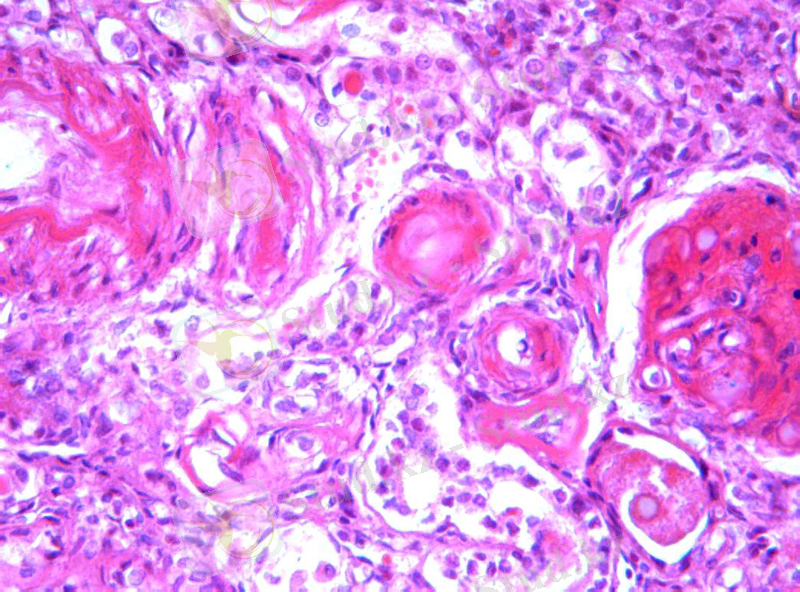

3 сурет. Гиалиноз

Гиалиноз - дәнекер ұлпасының біркелкі мөлдірлеу нығыз затқа айналуы.

Гиалин - күрделі фибрилярлы белок. Құрамында белок, гликозамингликан-дар және қан белоктары бар. Қышқыл, сілті, спирттердің әсеріне төзімді.

Гиалиноз жергілікті және жүйелі түрде дамиды. Қан тамырлар қабырғасында және дәнекер ұлпада кездеседі.

Микрокөрінісі: қантамырлар қабырғасы қалыңдайды, қуысы тарылады, құрылымы жойылып, біркелкі затқа айналады. Дәнекер ұлпада талшықар ісінеді, нығыздалып, шеміршекке ұқсаған массаға айналады.